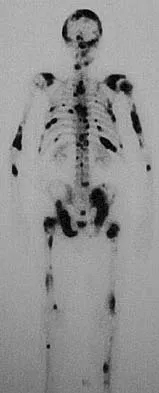

A 73-year-old man reports increasing back and lower extremity pain. A bone scan is shown in Figure 31. What is the most likely diagnosis?

The bone scan reveals lesions throughout the skeleton. The patient's age, gender, and pain pattern are consistent with metastatic prostate cancer. Multiple myeloma typically does not have enough osteoblastic activity to produce this bone scan. The patient's age is not consistent with metastatic neuroblastoma (a pediatric disease). Polyostotic fibrous dysplasia may involve multiple active lesions in younger patients but does not have such a widespread distribution of lesions. Hodgkin's lymphoma can involve bone, but the widespread discrete appearance on this bone scan is most consistent with metastatic prostate cancer. In a patient with widespread bone metastases from prostate cancer, bisphosphonates may play a critical role in treatment by decreasing pain and the number of fractures. Roudier MP, Vesselle H, True LD, Higano CS, Ott SM, King SH, Vessella RL: Bone histology at autopsy and matched bone scintigraphy findings in patients with hormone refractory prostate cancer: The effect of bisphosphonate therapy on bone scintigraphy results. Clin Exp Metastasis 2003;20:171-180.